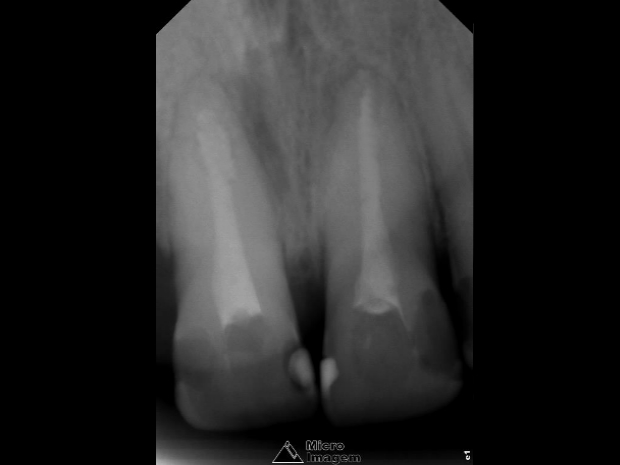

O mesmo relatava histórico de trauma dental na infância, sendo que previamente foi submetido a uma intervenção de urgência no elemento 21 por outro profissional, visto que se apresentava com edema e dor na região apical. Pela presença de fístula nesta região, foi realizado rastreamento na mesma, sendo a mesma oriunda do elemento dental 21 (figuras 2 e 3).

Após a abordagem inicial do paciente, o mesmo foi anestesiado e procedeu-se à confecção do isolamento absoluto. Posteriormente, o acesso coronário foi realizado, onde se constatou clinicamente a necrose pulpar de ambos os dentes. Foi realizada uma penetração desinfetante crown-down empregando como agente irrigador NaOCl a 5%, sendo a odontometria realizada pelo método radiográfico, devido a inviabilidade de emprego de um localizador foraminal nestas condições anatômicas, podendo influenciar em sua precisão (figura 4).

- Figura 2

- Figura 3

- Figura 4